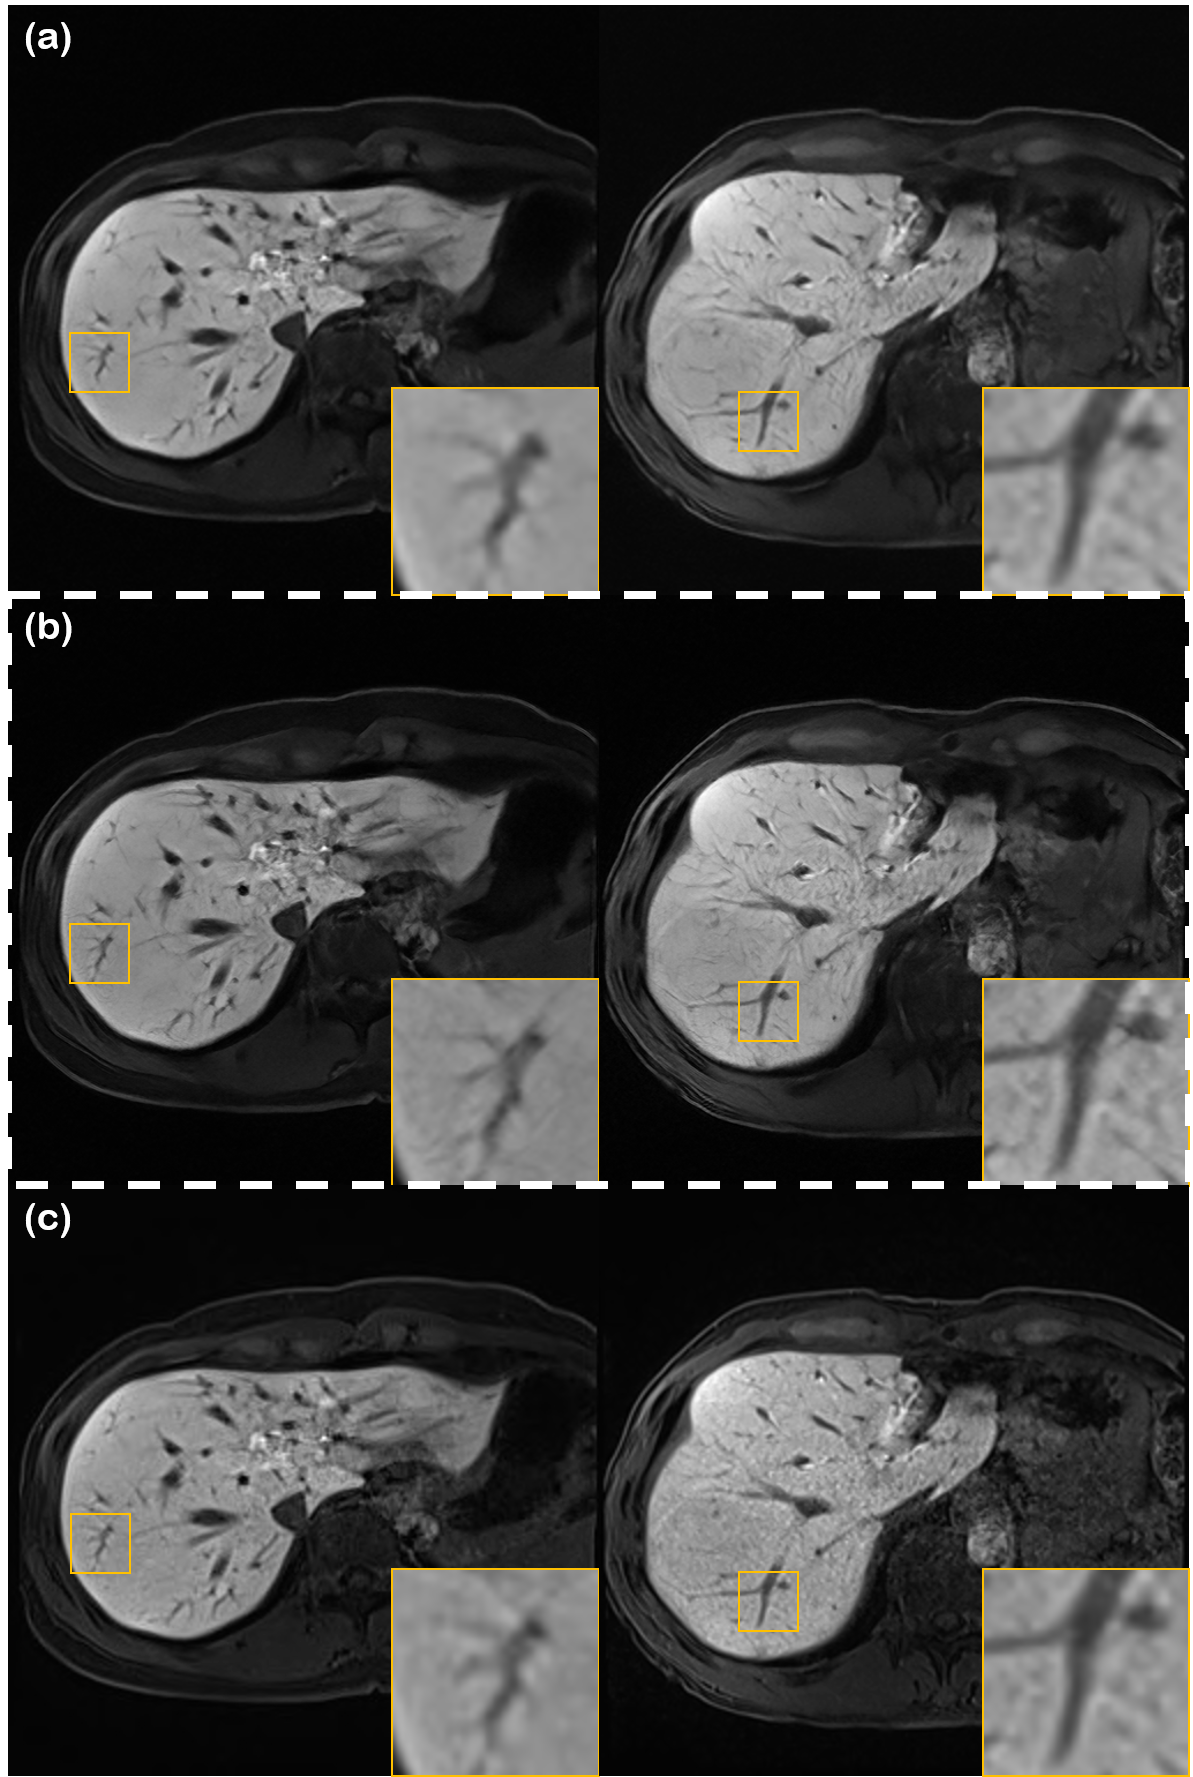

Refer to caption

Figure 1: Overview of the proposed reverse diffusion denoising scheme. Hijacking the reverse diffusion process leads to a strong denoiser. Our model is trained on open-source knee dataset [25], yet is scaled to in vivo liver MRI scans.

Leveraging such intriguing properties, we propose to use a score-based diffusion model [17] to solve the task of denoising. More specifically, we propose to hijack the generative process of diffusion models, not starting from pure Gaussian noise, but starting from the distribution of the noisy images. Illustrated in Fig. 1, this amounts to using the last few steps of the reverse diffusion, where the number of iterations can be approximated by parameter estimation methods [26]. Furthermore, to control the deniosing process, such that fine structures are preserved, we propose a novel low frequency constraint, which naturally connects to the recent theory of stochastic contraction in diffusion models [24].